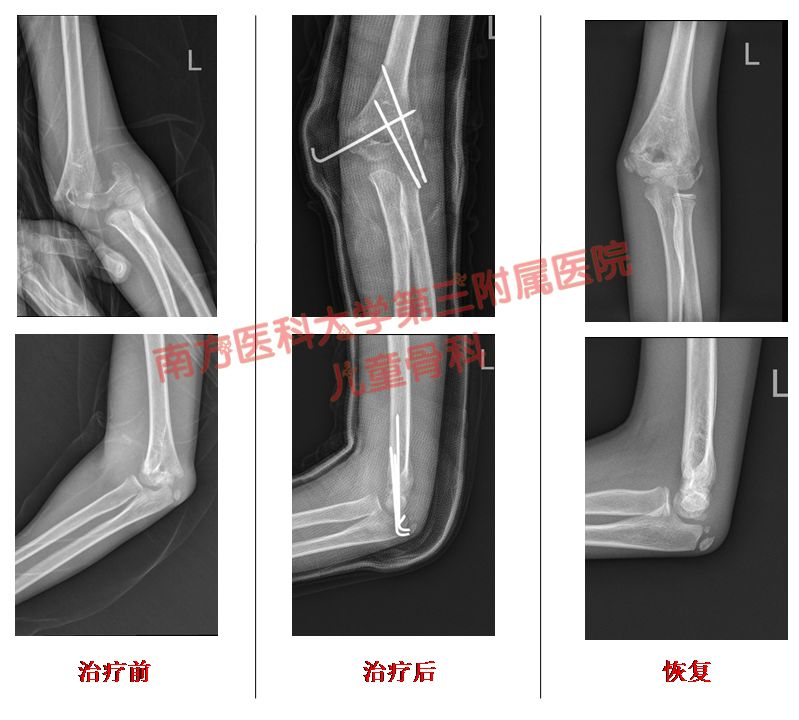

病例2

我科近乎“0”切开几率方式处理肱骨髁上骨折,麻醉下采用手法复位,克氏针交叉固定+石膏固定术,显著的减少了常规保守治疗肱骨髁上骨折高达30%的畸形率。